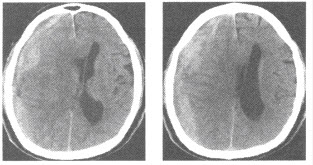

男,74岁,外伤1小时,意识模糊,平扫CT检查如图,最可能的诊断为()

A:硬膜外血肿

B:硬膜下血肿

C:蛛网膜下腔出血

D:脑内血肿

E:脑梗死